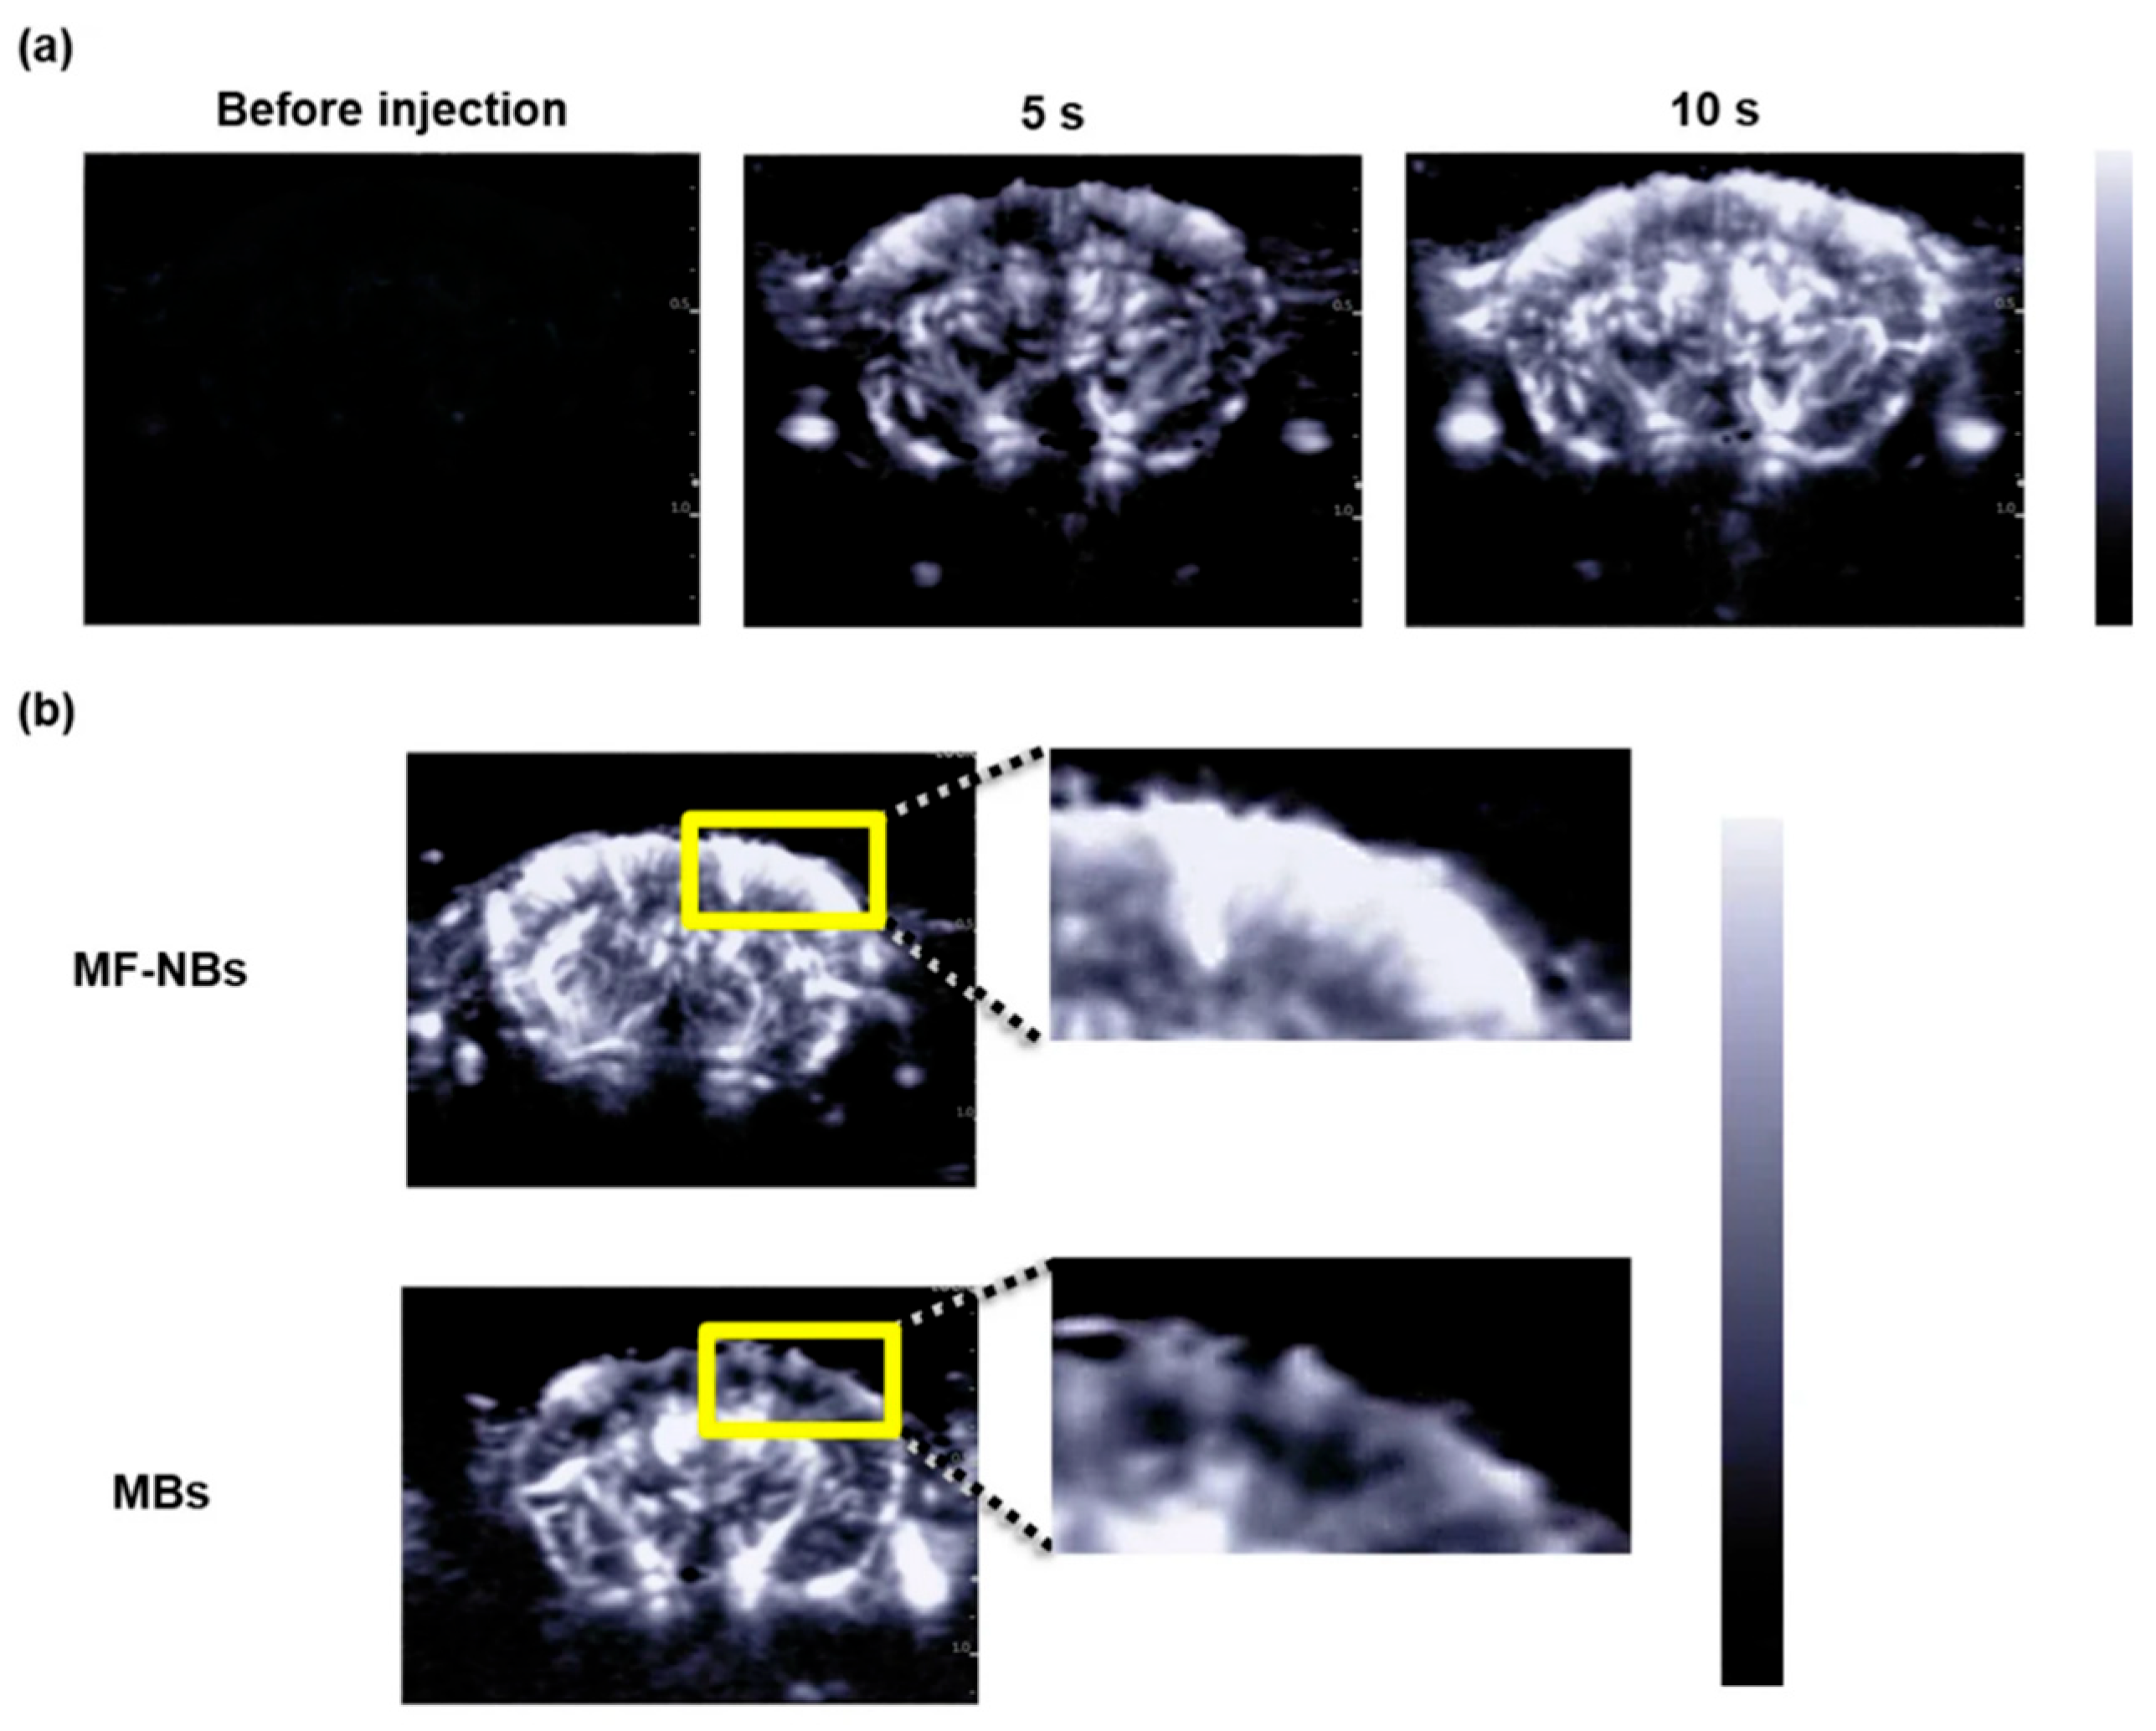

- Yamaguchi, T.; Endo-Takahashi, Y.; Awaji, K.; Numazawa, S.; Onishi, Y.; Tada, R.; Ogasawara, M.; Takizawa, Y.; Kurumizaka, H.; Negishi, Y. Microfluidic nanobubbles produced using a micromixer for ultrasound imaging and gene delivery. Sci. Rep. 2025, 15, 14871. [Google Scholar] [CrossRef]